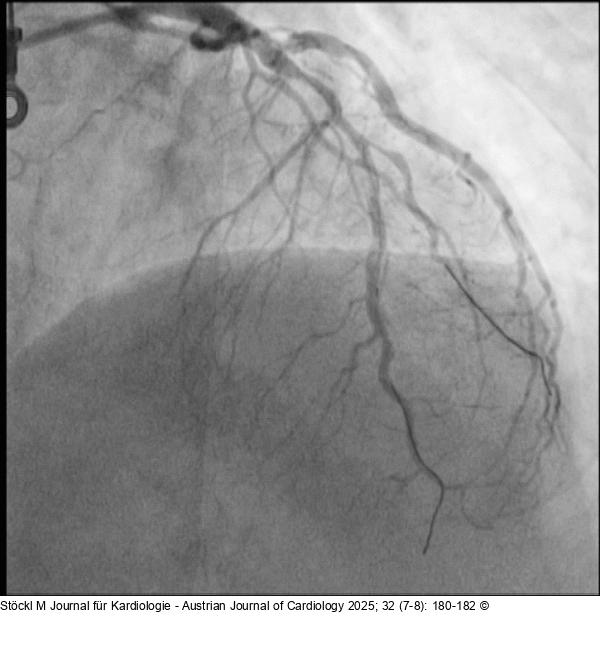

Abbildung 7: LAD: Ballon LAD: NEON™ NC 2,75/20 mm Ballon (Cordis): Dissektion |

Abbildung 7: LAD: Ballon

LAD: NEON™ NC 2,75/20 mm Ballon (Cordis): Dissektion |